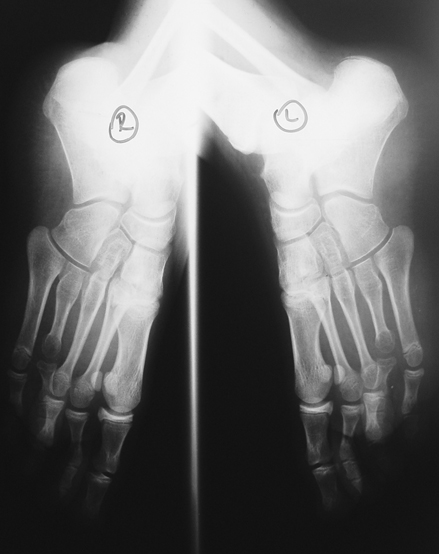

El parmağı (metakarp) ve ayak parmağı (metatars) kısalıkları doğuştan tek başına, geniş bir sendrom grubuyla birlikte, travma sonrası, Freiberg hastalığı (avasküler nekroz) sonrası görülebilir.

Doğuştan metakarp ve metatars kısalığının görülme sıklığı 1/1000’den azdır. Kadınlarda erkeklere göre 5 kat daha fazla görülür ve sıklıkla (%72) iki taraflıdır. En sık 4. parmak tutulur. Bu tür olgularda sorunun nedeni tam olarak bilinmemekle brlikte deformitenin genellikle epifiz plağının erken kapanmasından kaynaklandığı düşünülmektedir.

Doğuştan metakarp ve metatars kısalıklarının redavisi için pek çok teknik tanımlanmakla birlikte en çok akut uzatma sonrası kemik uçlarına greft konması ve distraksiyon osteogenezi (kallotasis) kullanılmaktadır. 1 cm.den daha fazla uzatma gereken olgularda kallotasis yöntemi önerilmektedir. Kliniğimizde de metatars ve metakarp uzatma için unilateral eksternal fiksatör ve sirküler eksternal fiksatör yardımıyla distraksiyon osteogenezi yöntemi tercih edilmektedir.